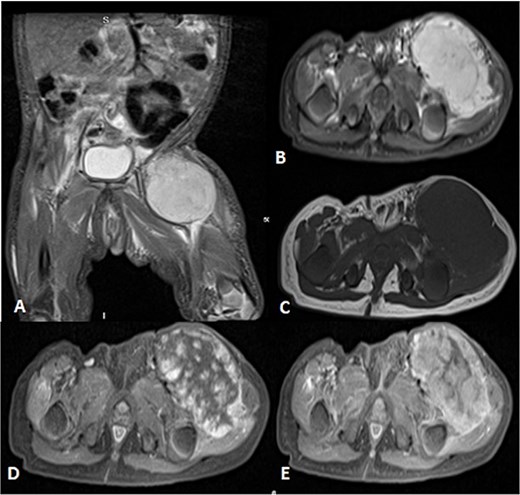

A 2-month-old girl was being followed for a suspected hemangioma on her left hand since birth. She was initially started on oral propranolol therapy but only received one dose, due to family concerns about possible side effects. The patient presented at the emergency room because of ulceration. It was observed clinically that the lesion had grown from 1.5 × 1.5 cm to 4 × 2 cm (Fig. 5). A biopsy of the lesion was taken. Ultrasound showed a partially defined large heterogeneously hyperechoic mass with internal vascularity on color Doppler with arterial and venous waveform giving atypical features of hemangioma (Fig. 6). Biopsy was done using FoundationOne Heme. The result showed stable microsatellite status and when we tested the tumor mutational burden, it showed two mutations per megabase. On MRI, a large lobulated subcutaneous soft tissue mass measuring 3.7 × 6.1 × 4.6 cm in dimensions was seen originating from the medial aspect of the left hand (Fig. 7). Internal flow voids, intermediate signal intensity on T1-weighted images, hyperintense signal on short tau inversion recovery (STIR)-weighted images, and noticeable heterogeneous enhancement on postcontrast sequences were all observed in the lesion. These imaging results raised suspicions of a malignant lesion.

MRI of left hand mass. (A) Axial T1WI shows a huge homogenous isointense mass to the corresponding hand muscles signal intensity, which is seen along the medial aspect of left hand. (B and C) Coronal STIR demonstrate heterogeneous diffuse high signal intensity of the lesion and appears inseparable with sign of invasion to the fourth and fifth digits extensor compartment/tendons as well as presence of areas of signal void (arrow). (D and E) Axial and sagittal post-contrast T1 fat-saturated images show diffuse progressive intense enhancement of the lesion.